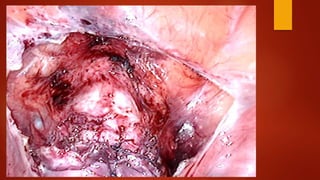

Суть метода После вскрытияпузырно-маточной складки брюшины и низведения мочевого пузыря при помощи монополярного электрода типа «Игла» рассекается рубец.

Края рубца «освежевываются»с помощью ножниц без использования энергий. Далее стенки матки ушиваются синтетической рассасывающейся нитью «Викрил» №1 отдельными швами в два ряда. Перитонизация.